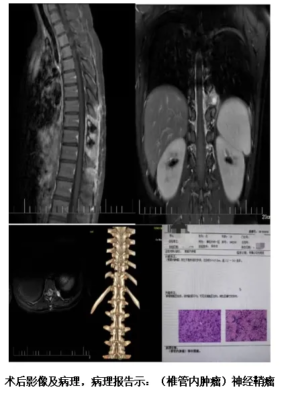

胸椎增强+MRA示胸10-11椎体左旁髓外硬脑膜下占位,神经鞘瘤可能性大。